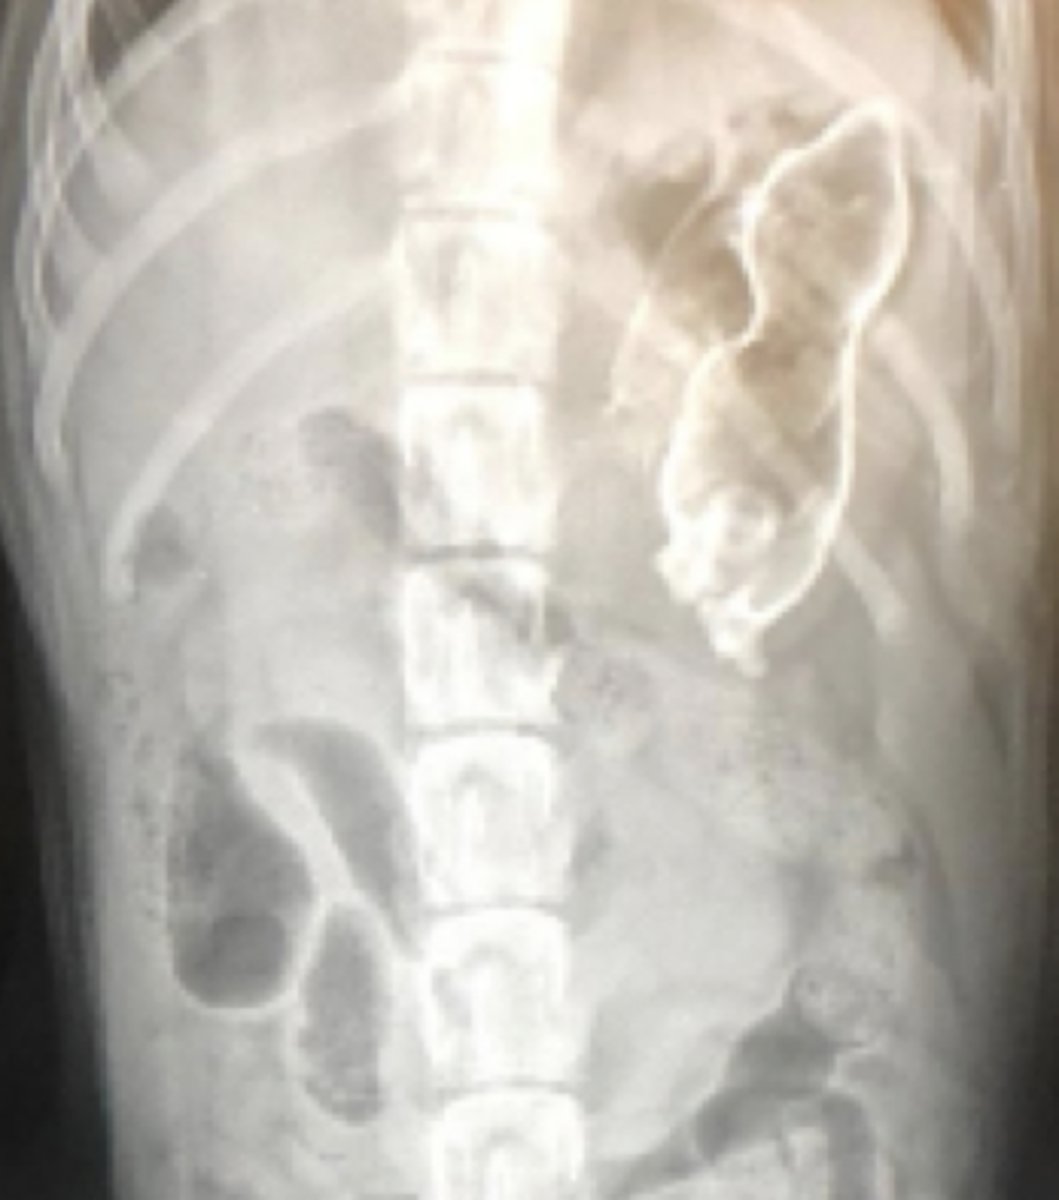

colelitos

(opacidad mineral, nivel hígado)

patología:

(hiperecoico, con sombra)